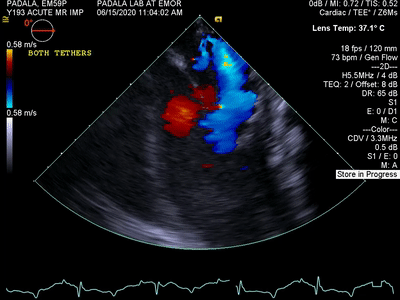

增大的天然瓣葉增加了瓣膜的接合表面,并消除了反流。幾周后,CARLEN植入物被內(nèi)皮化組織層吞沒,提供了適合患者瓣膜幾何形狀的局部增強天然瓣葉,解決了大量患者的問題。

植入前

植入后

植入后 30 天內(nèi),CARLEN已經(jīng)內(nèi)皮化并在其上形成一層薄薄的天然組織。這使得CARLEN擁有有非常好的血液相容性,并且無需使用血液稀釋劑。瓣葉仍然非常柔韌,并且保留了植入物的活動性。